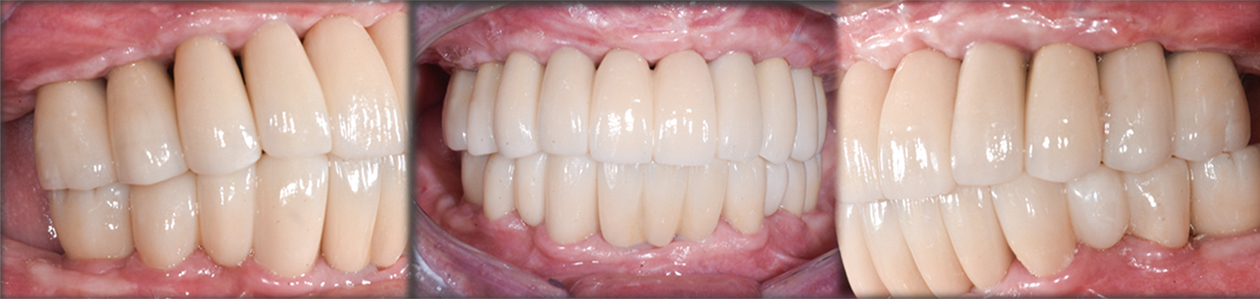

牙科數位科技的發展讓精準醫療概念逐步落實,透過臉部掃描、口內掃描以及動態面弓的協助,醫師能更有效地制定符合病人需求的治療方案。例如,透過臉部掃描以及口內掃描的結合,醫師不僅可以將每個人臉部與牙齒的座標資訊整合到贋復軟體中,接著透過數位微笑設計的理念替每個人設計出獨有的牙齒外型,除了可以透過影像讓病人看到未來的規劃,也可將數位的診斷設計檔列印成為3D模型,並於病人口內製作及試戴,確定病人滿意這樣原型的美觀、功能和發音後,即可進行後續的假牙製作。另外,在口內掃描及動態面弓的協助下,可以記錄病人適應後的臨時假牙當下運動狀態、臨時假牙外型,提供未來正式假牙設計的參考。最後再透過數位軟體協助製作客製化的臨時牙外型及動態運動的假牙,使病人有較佳的舒適度與功能。

│3D 列印植牙靜態導板與動態導航在臨床上的應用

3D 列印技術在牙科的應用日益成熟,其中,電腦輔助靜態植牙手術導板(Computer-Assisted Surgical Guide)對於提升植牙手術的精準度與效率有極大幫助。透過數位口腔掃描與電腦斷層3D影像,醫師可以先在電腦上模擬植牙位置,並透過 3D 列印技術製作專屬於病人的植牙導板。此技術能確保植體位置、角度與深度的準確性,降低醫師在手術過程中的誤差,同時減少病人的手術創傷與恢復時間。此外,3D 列印植牙導板特別適用於多顆植牙或全口無牙的病人,能提升植體的長期穩定性與成功率。(圖一~圖五) 此外,除了靜態導版,動態植牙導航技術 (Navigation)的發展,更是植牙手術的一大躍進!